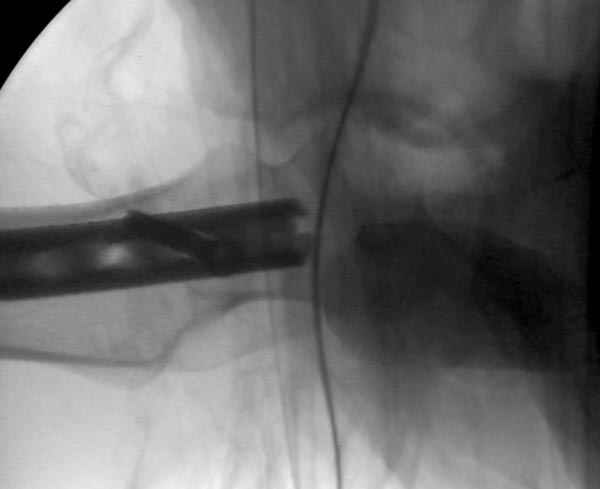

Больной долго оставался нестабильным, только на 14 день удалось заменить на антеградный интромедуллярный штифт TFN (trochanteric femoral nail) SmithNephew. После неудачной попытки закрытой репозиции, несмотря на использование "joystick", проксимальный стержень от

наружного фиксатора, (перелом начал срастаться) репозицию провели из малого доступа, затем остальные этапы операции.

Случай был представлен из-за того, что больного оперировали после наружной фиксации и был риск инфекцирования через места проведения стержней (на снимках), прошло больше 3 месяцев, выписан из амбулаторной службы из-за отсутсвия надобности дальнейшего наблюдения.